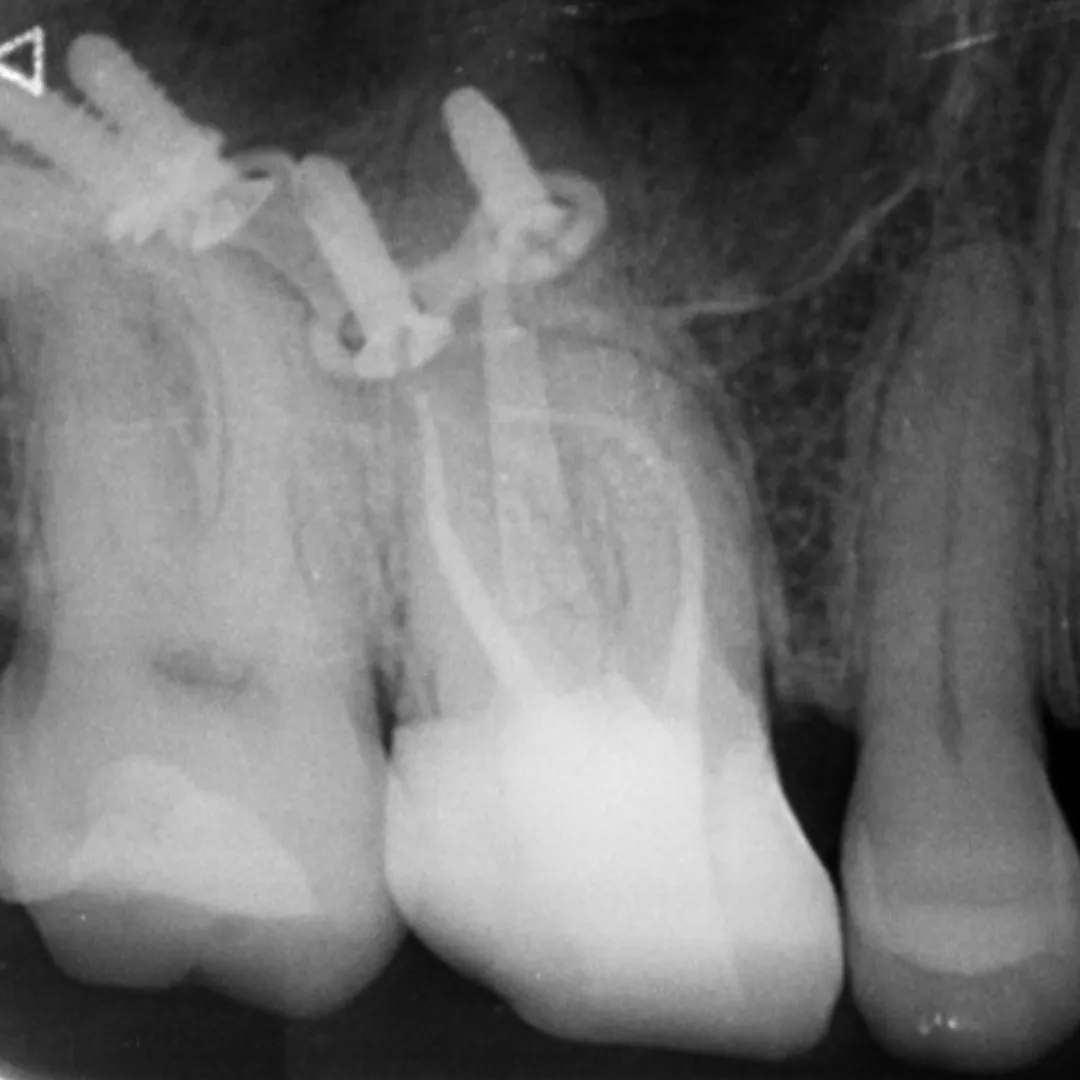

• Management of curved canals, calcified canals, and difficult access cases.

• Re-treatment cases of non-healing or failed root canals.

• Managing perforations, ledges, or instrument separation.

• Advanced use of CBCT and magnification (microscope) for navigation.